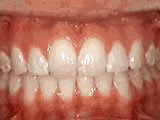

Spacing of teeth

Patient was bothered by the spaces between his teeth. Braces closed the spaces and gave him an ideal bite in 24 months. Special glued-in retainers help keep the spaces closed.